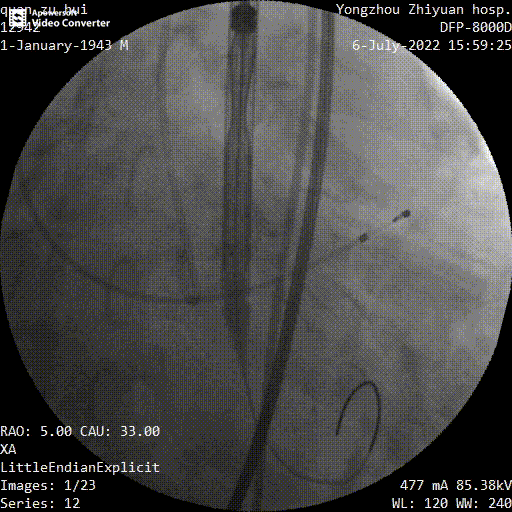

主动脉根部造影

球囊预扩

瓣膜定位

释放到工作位

多角度观察

最终释放

手术过程中,在完成跨瓣操作后,23mm球囊预扩有轻微腰征、无造影剂渗漏,预装TaurusElite AV29瓣膜到位,输送系统快速、顺利地完成过弓、跨瓣操作,于瓣环上约2mm定位释放;针对本例患者瓣叶明显增厚伴重度钙化,左右窦间可见钙化融合嵴的特点,TaurusElite瓣膜高密度流入端设计提供了足够的径向支撑力,保证了瓣膜的锚定力,瓣膜内外双裙边设计能提供良好的辅助锚定力,有效减少瓣周漏。此外,本例患者左窦间存在长条状钙化延伸至瓣环下10mm水平,释放位置偏深可能存在起搏器植入风险,TaurusElite瓣膜具有多次完全可回收,回收后可重新跨瓣、释放的特点,给予术者足够的信心完成高位释放的操作,释放后最终瓣架底端位于瓣环下约1mm,实现了释放位置的精准控制,有效的减少了起搏器植入风险,确保了手术安全、顺利的完成。这例手术为永州地区开展的第一台TAVR手术,填补了该地区TAVR技术空白,标志着永州市心脏瓣膜疾病诊治迈入了全新的微创治疗时代!